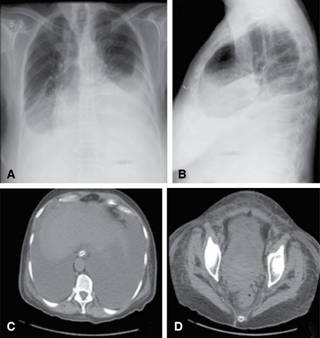

A 64-year-old Brazilian woman was admitted on January 24th 2016 because of abdominal distension causing progressive breathlessness with two months of duration. She had noticed changes in her bowel function, with alternate constipation and diarrhea. Before admission, a chest radiography showed bilateral pleural effusion; and abdominal computed tomography revealed an extensive hypogastric mass with central areas of necrosis and involving adjacent small and large intestinal bowels. In addition, there was massive ascites, and infra diaphragmatic bilateral lymph node enlargement (Figure 1). On admission, she claimed abdominal pain and presented with tachycardia and dyspnea. Physical examination revealed BMI: 29 kg/m2, normal heart function, pleural effusion and ascites, absence of visceromegaly and of lymph node changes, or peripheral edema. Diagnostic thoracentesis and paracentesis were done with suspicion of Meigs’ syndrome. Pleural fluid was a transudate and malignant cells were not observed in pleural specimens, whereas ascites was clearly carcinomatous. Routine tests showed: hemoglobin 13.7 g/L, hematocrit 42.1%, leukocytes 5.18 × 109/L, platelets 476 × 109/L, urea 12.7 mg/dL, creatinine 0.6 mg/dL, AST 55.4 U/mL, ALT 37.5 U/mL, ESR 61/1ah, C-reactive protein 5 mg/dL; the rest of biochemistry was normal. Worthy of note was the elevated level of CA 125: 6,973.0 U/mL (reference: < 35 U/mL). Pulmonary computed tomography angiography ruled out lung thromboembolism, and showed bilateral pleural effusion. PET-CT scan detected hypermetabolic foci indicative of neoplastic involvement in the hypogastric mass, in abdominal and thoracic lymph nodes, and in the first left rib; in addition to smooth and nodular inspissation in some peritoneal and pleural locations. Exploratory laparotomy revealed a large hypogastric tumor (9.9 cm x 9.7 cm x 7.4 cm) without plans of cleavage, and omental caking that indicated peritoneal carcinomatosis. Histopathology findings from samples obtained of the peritoneum as well as of the tumor were consistent with the diagnosis of HGSOC (Figure 2). Immunohistochemistry: cytokeratins 40, 48, 50 and 50.6 kDa (AE1/AE3) positive; estrogen receptor (SP1) positive; PAX8, transcription factor of the family of gene-paired box [PAX] (MRQ50) positive; and product of oncogene Wilms Tumor 1 [WT-1] (6F-H2) positive. Additionally, the CDX2, intestinal transcription factor (EPR2764Y) and TTF-1, thyroid and lung transcription factor (clone 8G7G3/1) were all negative. The possibility of surgical approach was discarded. Therefore, patient was referred to outpatient Oncology care, and underwent chemotherapy with paclitaxel and carboplatin. It is worth noting that the patient’s general condition as well as ascites and hydrothorax had progressively improved on the course of chemotherapy. Therefore, the patient did not undergo further thoracentesis since her hospital discharge. Currently, approximately 10 months after beginning of specialized follow-up, no recurrence of ascites or significant pleural effusion was revealed by routine radiographic control (Figure 3).

Figure 1: A and B: Chest radiograph showing accentuated bilateral pleural effusion; and abdominal CT revealing massive ascites (C); and voluminous hypogastric mass with areas of necrosis, bilaterally involving adjacent organs and local lymph nodes (D).